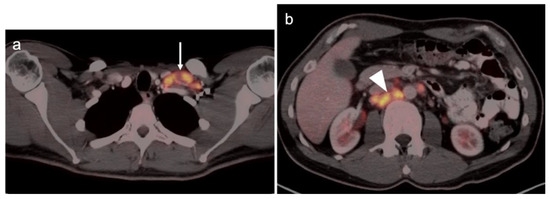

3.1. Prostate Cancer

3.3. Primary Testicular Cancer